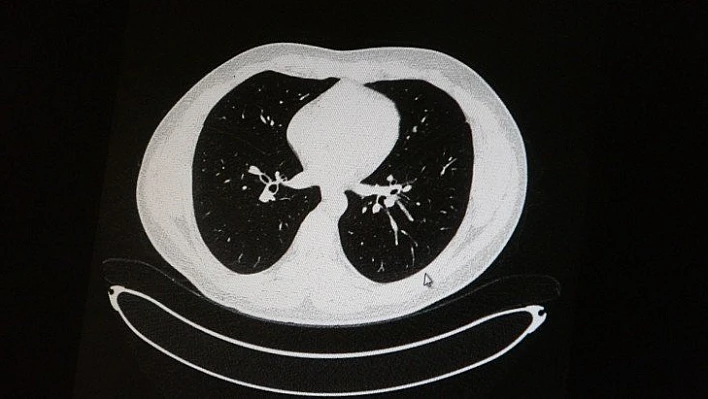

Elazığ'da öksürük, halsizlik, yorgunluk ve çabuk yorulma gibi şikayetlerle hastaneye başvuran ve korona virüs tespit edilen 2 genç hastadan aşısız olanının tomografi sonuçlarında virüsün akciğerlerde zatürreye sebebiyet verdiği görüldü. Aynı şekilde aşı olup korona virüs hastalığına yakalanan bir başka genç hastanın bilgisayarlı akciğer tomografisinde akciğerinde herhangi bir sorunun olmadığı belirlendi.

Medical Park Elazığ Hastanesi Göğüs Hastalıkları Uzmanı Dr. Cebrail Azar, geçtiğimiz yıla oranla yoğun bakımda yatan hastaların yaş ortalamasının 65’ten 35’lere kadar düştüğüne dikkat çekti. Genç olduğu halde aşı olmayanlarda hastalığın ağır seyrettiğini ifade eden Uzm. Dr. Azar, "Ben gencim, benim bağışıklık sistemim kuvvetli" diyen genç bir hastanın akciğerlerinde ciddi lekelenmelerin olduğunu ve korona virüs zatürresi olduğunu gördüklerini belitti. Uzm. Dr. Azar, aynı şekilde aşı olup korona virüs hastalığına yakalanan bir başka genç hastanın akciğer tomografisinde akciğerde herhangi bir sorunun olmadığını ve hastanın durumunun iyi olduğunu gözlemlediklerini kaydetti. Uzm. Dr. Azar, sürekli şahit oldukları "Keşke biz aşı olsaydık" sözünü bir daha duymamak için herkesi aşı olmaya davet etti.